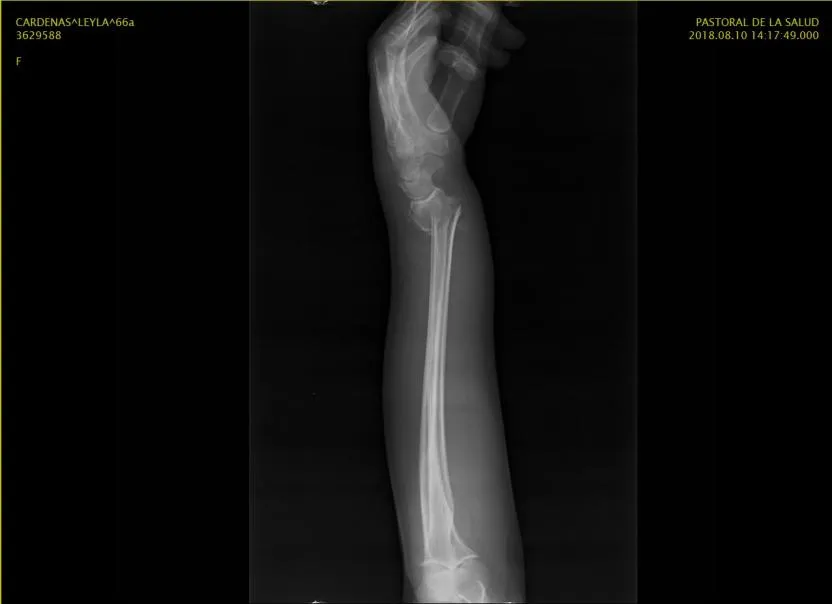

El día Viernes 10 de Agosto del presente año una gran amiga de la familia, madrina de dos de mis hijos, sufrió una fuerte caída afectando su mano Izquierda presentado Fractura de 1/3 distal del radio con desplazamiento del fragmento distal en sentido posterior y radial.

Mando a solicitar las imágenes de RX para ver que estaba sucediendo el día Domingo. mi querida amiga vive en otra ciudad no muy lejos de la mía pero aun así pues estaba un tanto lejos, así que mi papá le toco viajar para buscar las imágenes y cuando las reviso me pareció raro el diagnostico del medico, no porque no fuera grave sino porque estaba solicitando una cirugía que a mi parecer no iba al caso. Para muchos es conocido que trabaje por varios años en el área de salud como analista de seguros en el área de clave de emergencia, ademas de ser supervisora de admisión en una clínica, me toco revisar muchos casos para no decir cientos de ellos, donde evalué diagnósticos similares y me tocaba decidir si procedía el ingreso o no a cirugía.

Estas son las imágenes de Rx de mi amiga

A mi parecer este tipo de traumatismo solo llevan una maniobra que lleva el hueso a su lugar y se le coloca un yeso para mantener protegida la zona mientras se hace el proceso de sanación de la zona afectada, pero como no soy traumatologa no puedo afirmar o desmentir a un especialista. Acto seguido llamo a la clínica de traumatología en donde trabaje como supervisora de admisión, en la cual siempre me han atendido con un amor incondicional debido a todo los buenos momentos que allí pase, converso con mi antigua jefa (cabe destacar que es una excelente persona con un carisma impresionante) y le pido ayuda para que un medico de la clínica atendiera el caso y me diera su evaluación.